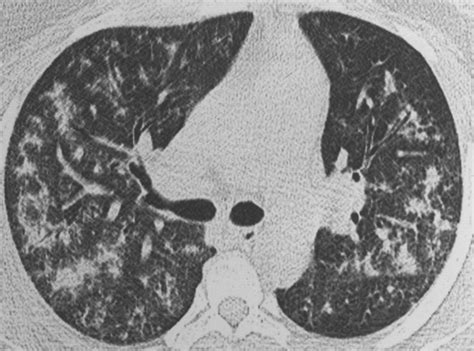

• Chest X-ray or CT scan

• bird fancier lung x ray

• bird fancier's lung radiology